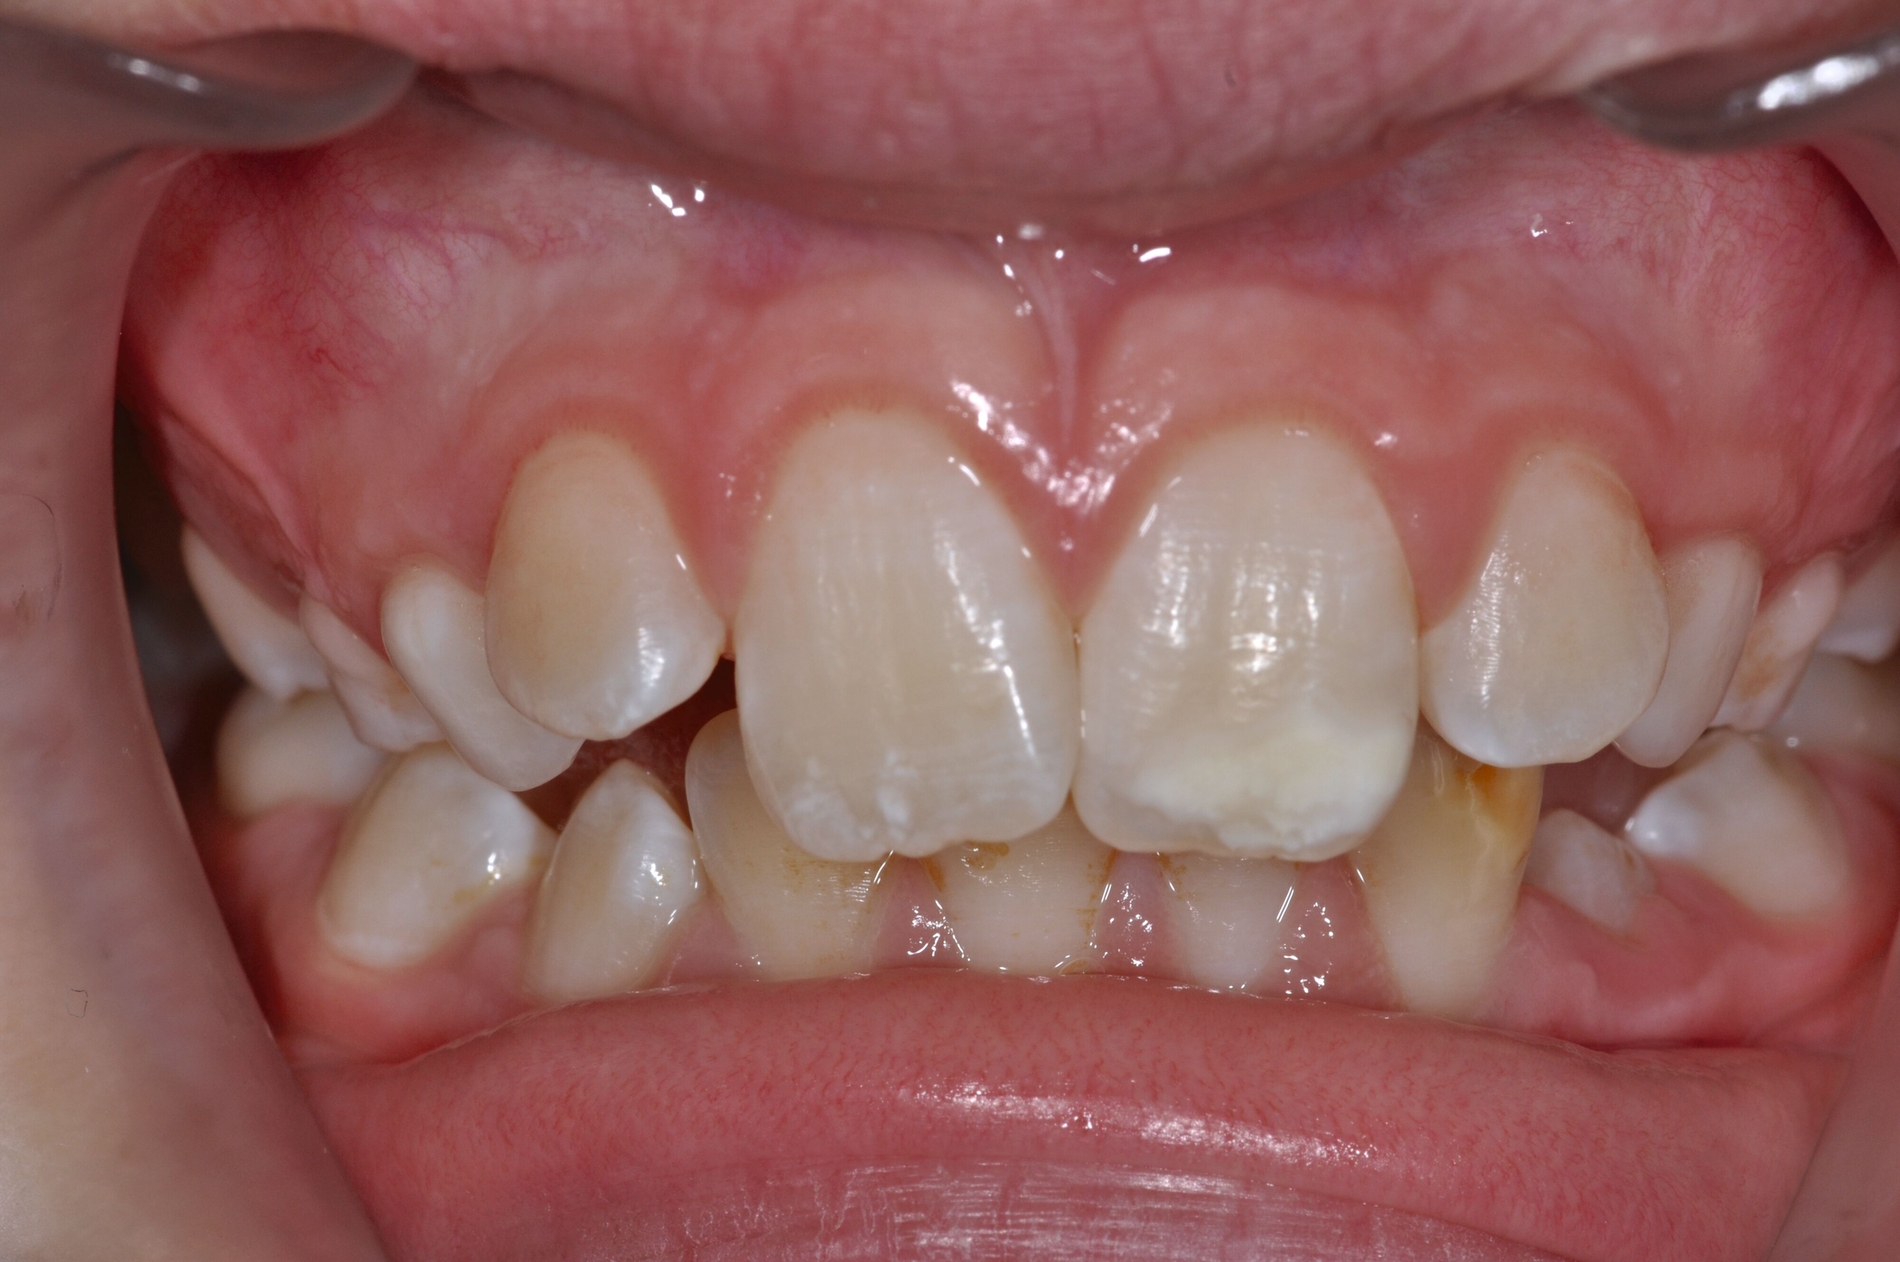

Diese Klassifikation dient als Grundlage für die Therapieempfehlungen. Deutlich wird, dass aufgrund der Symptomatik die Therapie der Zähne höchst unterschiedlich ausfällt. Dass etwa eine Opazität ohne Überempfindlichkeit (Index 1, Abbildung 1) ein anderes therapeutisches Vorgehen erfordert als ein Zahn mit nahezu komplettem Einbruch der Zahnoberfläche und mit Hypersensitivität (Index 4, Abbildung 2), ist offensichtlich.

Für die zahnärztliche Praxis gibt die Einteilung eine Orientierung darüber, welche Behandlungsmaßnahmen erforderlich sind beziehungsweise eingesetzt werden können. Je nach Schweregrad wird dabei zwischen nichtinvasiven und invasiven Maßnahmen sowie einer kurzzeitigen oder längerfristigen, restaurativen Therapie unterschieden. Bei der Überarbeitung des Konzepts wurde zudem zwischen Front- und Seitenzähnen differenziert (Abbildung 3) [Bekes et al., 2023; Steffen et al., 2017].